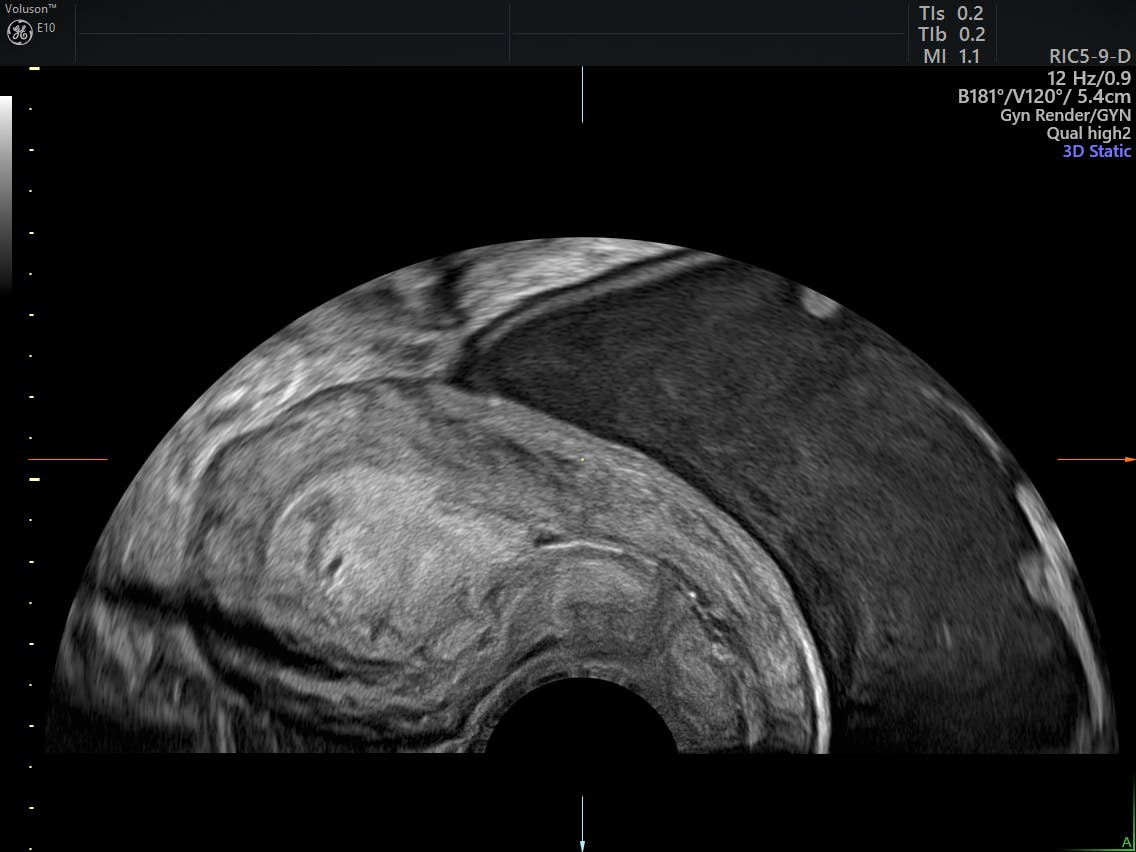

What Were Your First Signs Of Endometrial Cancer / 3 Signs Of Prostate Cancer You Should Never Ignore - YouTube / This happens in almost all women with.. Care guide for endometrial cancer. Endometrial cancer is cancer of the endometrium, which is the lining of the uterus. Endometrial cancer is a type of cancer that begins in the uterus. However, experts believe that changes in the level of estrogen and progesterone in the body often play a part. Some people who have endometrial cancer will be asymptomatic — showing no symptoms — until the disease spreads to other organs in their body.

Endometrial cancer is a cancer that arises from the endometrium (the lining of the uterus or womb). Endometrial cancer starts in the lining of the uterus (endometrium). Endometrial cancer is a type of cancer that begins in the uterus. Endometrial cancer is detected at an early stage because it frequently produces vaginal bleeding this is the most common sign that you are boarding towards endometrial cancer. Contact your doctor if you have: However, experts believe that changes in the level of estrogen and progesterone in the body often play a part. Most uterus cancers are in fact endometrial cancer. Different stages representing symptoms of endometrial cancers. Endometrial cancer is the 10th most common cancer in the united states. The second, or type 2 (comprising the remaining 20%), does not appear to have any linkage to estrogen stimulation and therefore does not have the typical. The first, or type i, is linked to estrogen stimulation and comprises 80% of the cases. There are other cells in the uterus that can risk factors, signs and symptoms. Menstrual bleeding that is heavier or lasts longer than usual.

Signs and symptoms of endometrial cancer include unusual vaginal bleeding or pain in the pelvis. Endometrial cancer is sometimes called uterine cancer. It is the result of the abnormal growth of cells that have the ability to invade or spread to other parts of the body. Approximately 75% of women with endometrial cancer are postmenopausal. There are other cells in the uterus that can risk factors, signs and symptoms. And the treatment for this uterine cancer is commonly surgery to remove the uterus. Menstrual bleeding that is heavier or lasts longer than usual. Endometrial cancer begins in the layer of cells that form the lining (the endometrium) of the uterus (see figures 1 and 3). Abnormal bleeding happens in most of the endometrial cases. Endometrial cancer, the main type of uterine cancer, starts in the cells that make up the endometrium—the lining of the uterus that is the first is an endometrial biopsy. your doctor will remove a few cells of the endometrium, usually in the office, to study them under a microscope and. What are the symptoms of endometrial cancer? Can endometrial cancer be found early? The number of women diagnosed with uterine cancer has increased in recent the sooner endometrial cancer is found, the better is the outcome.